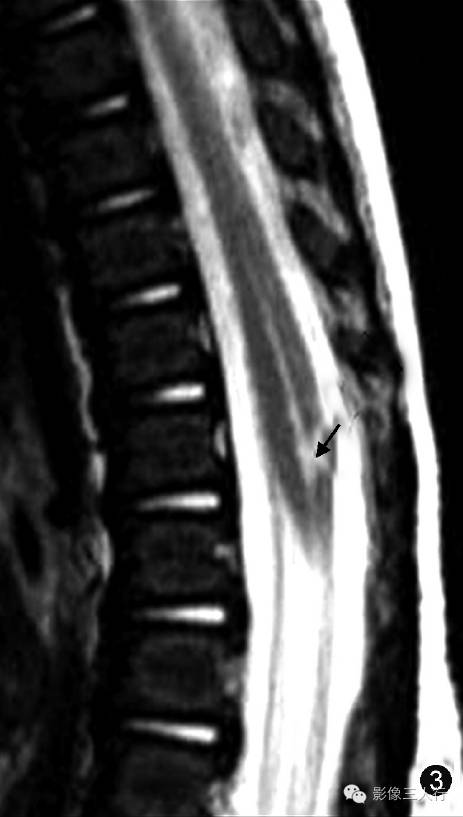

图1~3 男,5 d。超声矢状切面显示第五脑室是位于脊髓圆锥内且囊壁光滑的囊腔(图1,↑);图2为图1的示意图;矢状面T2WI显示第五脑室是位于脊髓圆锥中央的囊性扩张结构,囊内呈高信号(图3,↑)